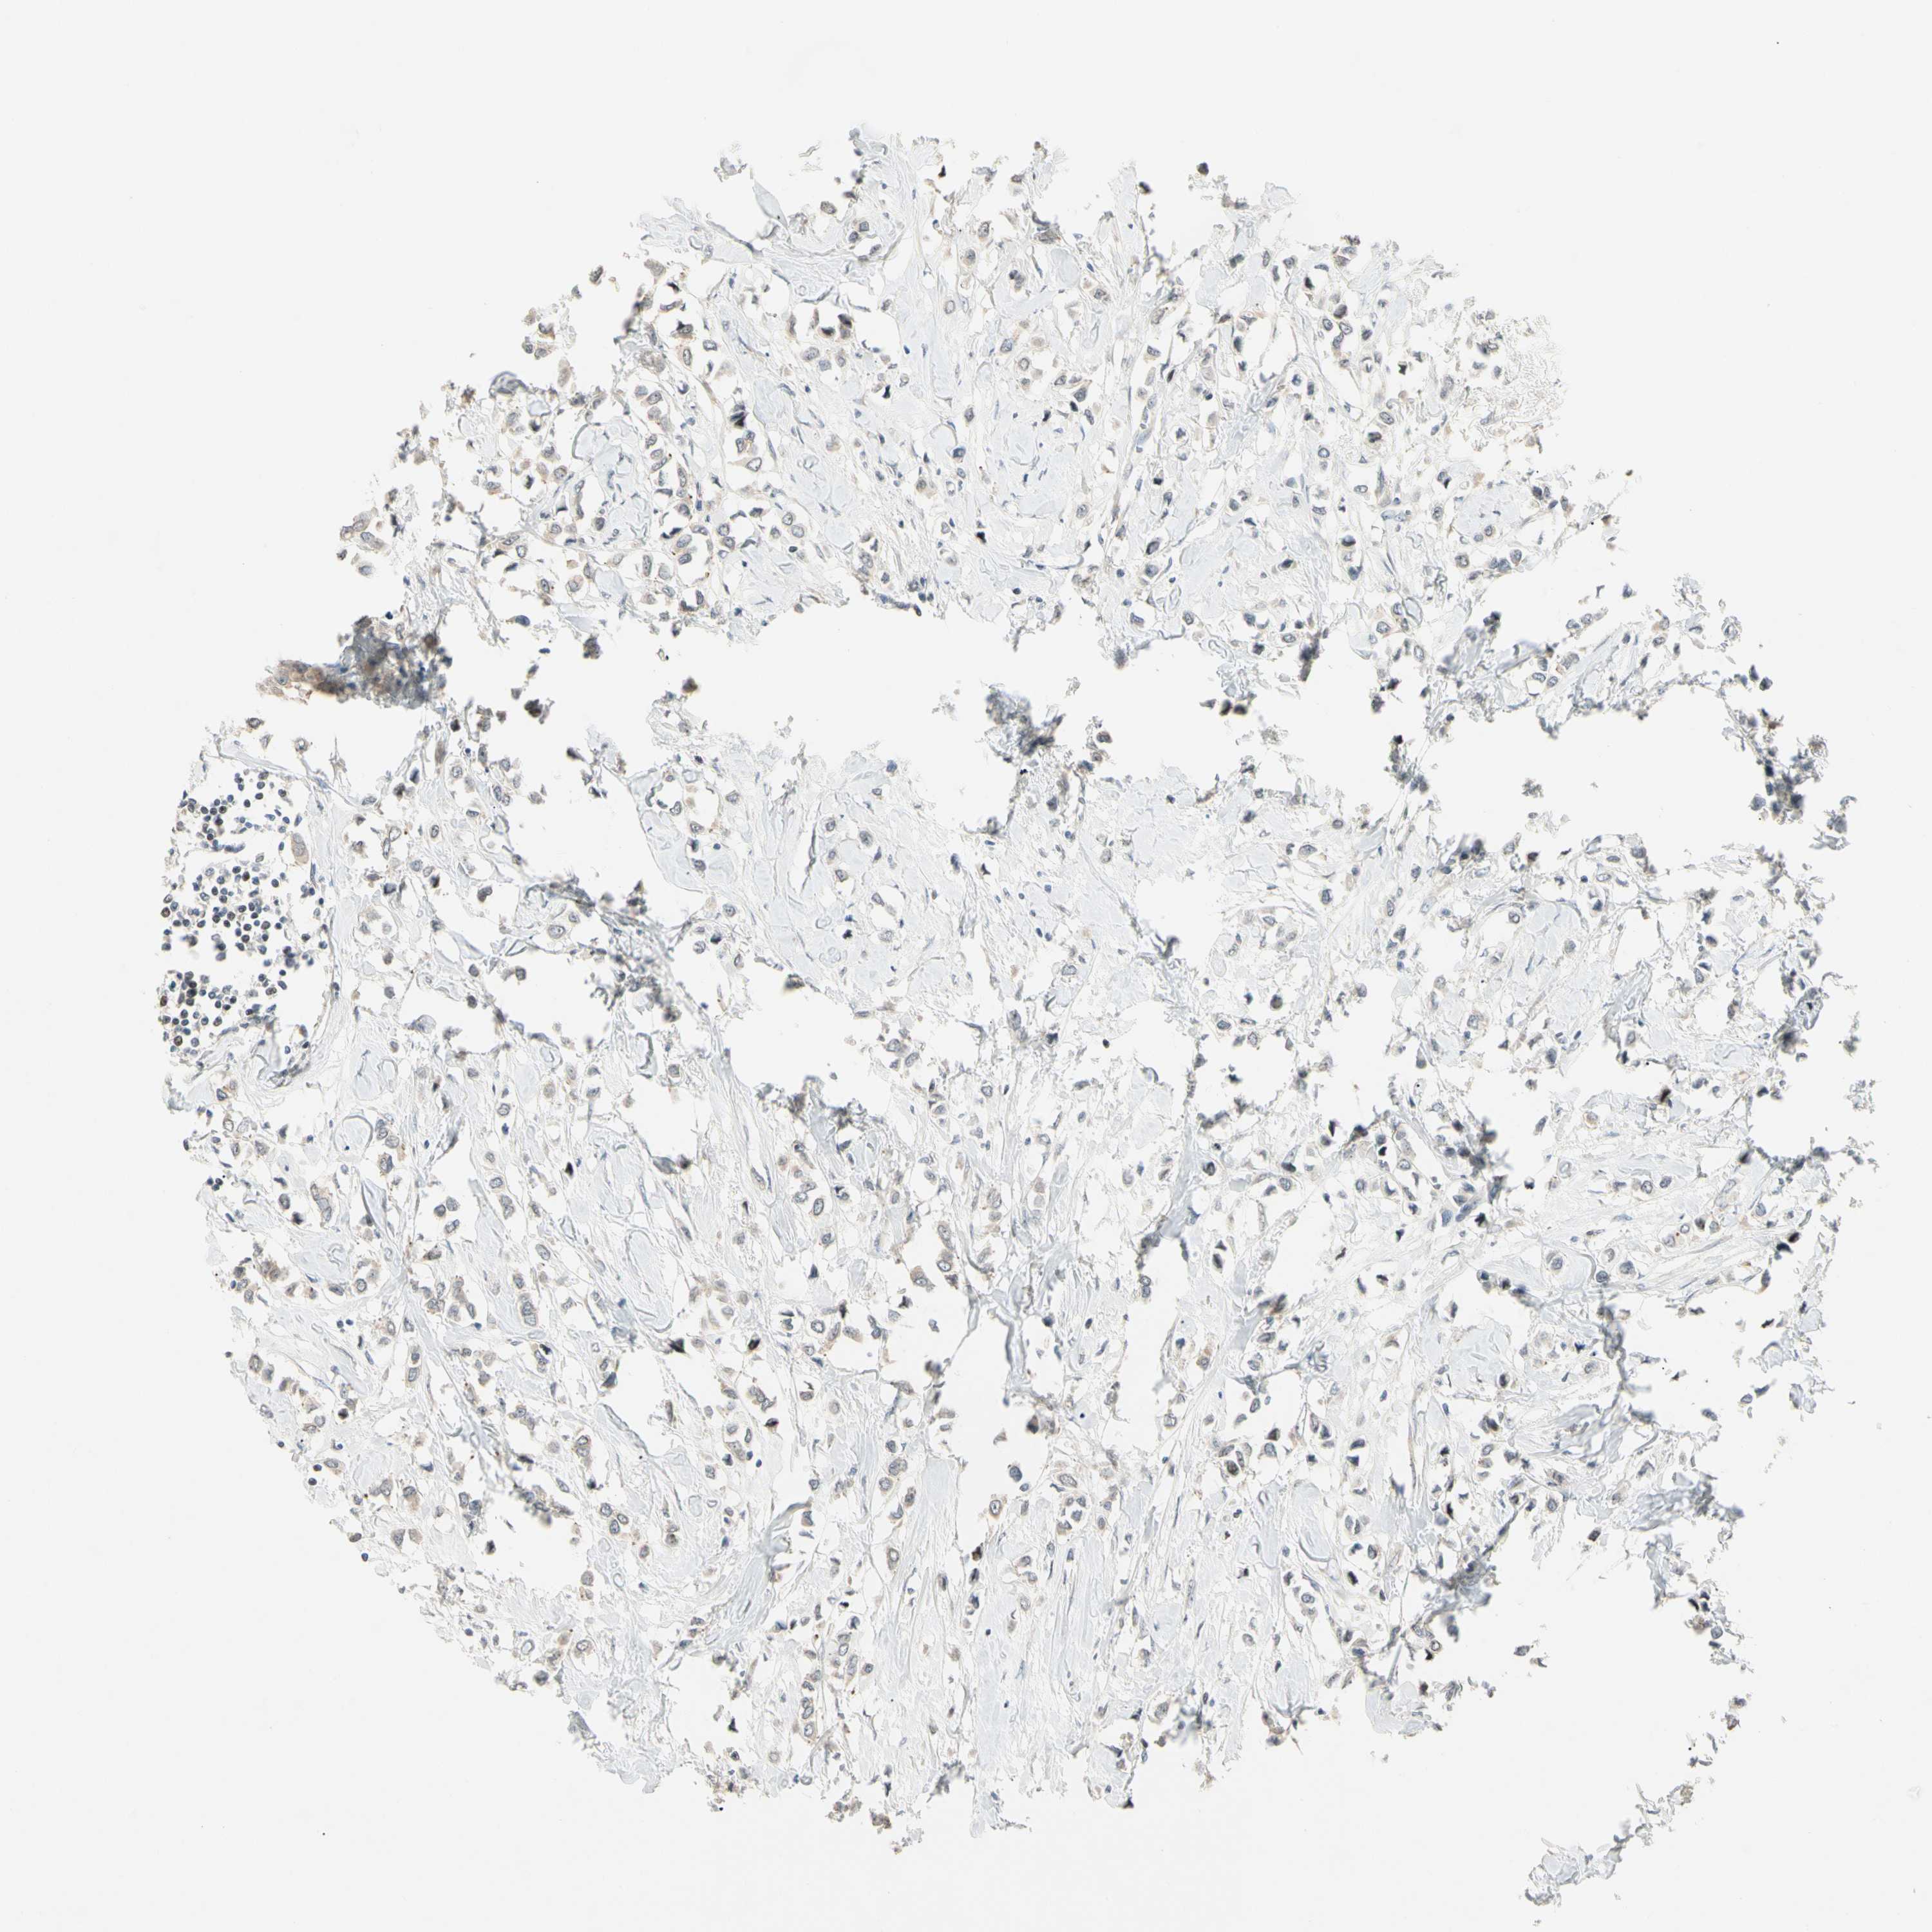

CANCER BREAST CANCER Show tissue menu

BRCA TCGA BRCA VALIDATION PROTEIN EXPRESSION